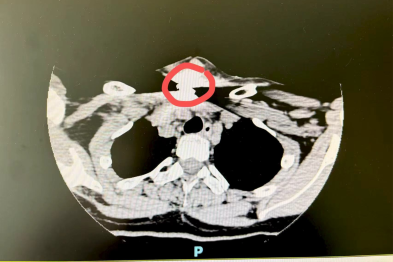

「胃不适」原是 20 厘米肿瘤侵犯心脏大血管 医生冒险手术挽回年轻生命